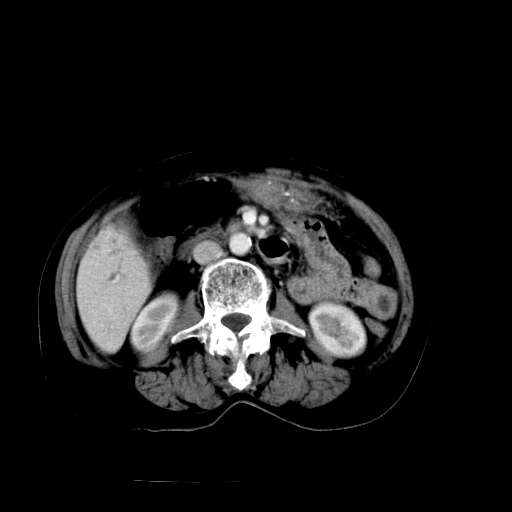

以下是引用随光逐影在2009-4-7 8:21:00的发言:[br]肝内外胆管多发性结石并肝内外胆管扩张;胆系感染。